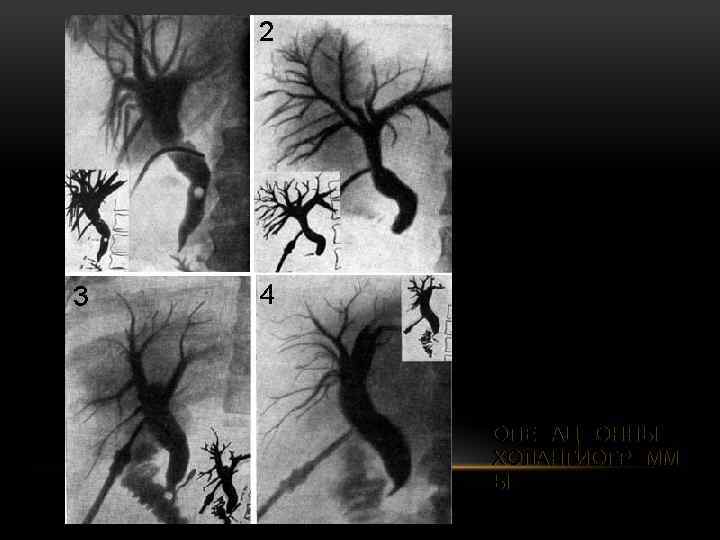

ОПЕРАЦИОННЫЕ ХОЛАНГИОГРАММ Ы

ОПЕРАЦИОННЫЕ ХОЛАНГИОГРАММ Ы